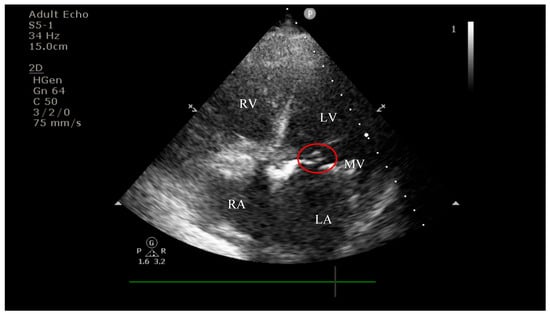

4.2. Diagnostic Findings: Mitral Valve Dysfunction and Embolic Phenomena